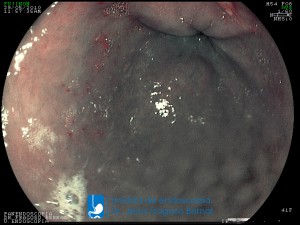

La Unidad de Endoscopía fue creada en 2002 por el Dr. Jesús Fragoso Bernal, es pionera en el estado por la utilización de la tecnología más avanzada, que nos permite ofrecer servicios integrales de diagnóstico y tratamiento para las enfermedades del aparato digestivo.

"La Unidad de Endoscopía se ha caracterizado por un progreso continuo desde su inicio marcando la pauta en los procedimientos endoscópicos en el estado de Tlaxcala y estando siempre a la vanguardia tecnológica."

Dr. Jesús Fragoso Bernal